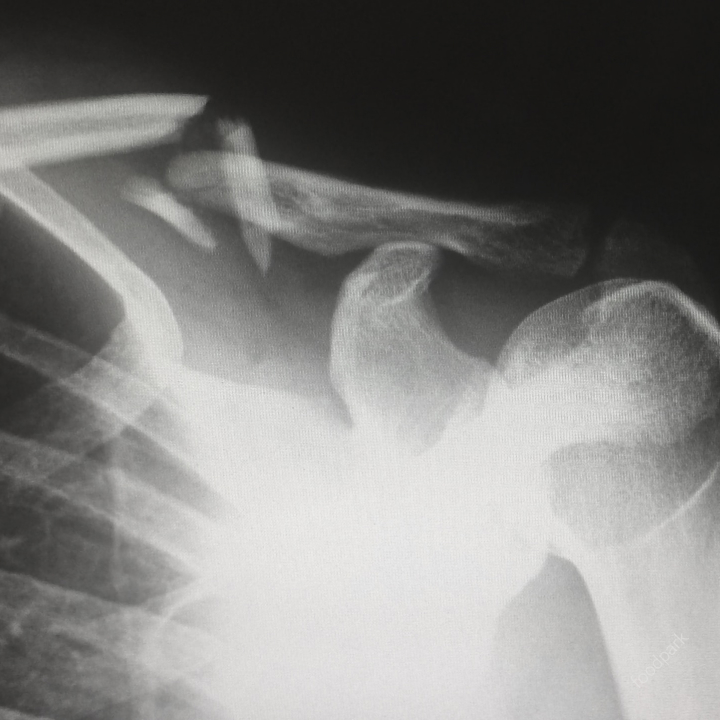

골감소증이 있는 사람은 특히 엉덩이, 척추 및 손목에서 골절 위험이 더 높습니다. 이러한 골절은 고통스러울 수 있으며 치유하는 데 오랜 시간이 걸릴 수 있습니다.